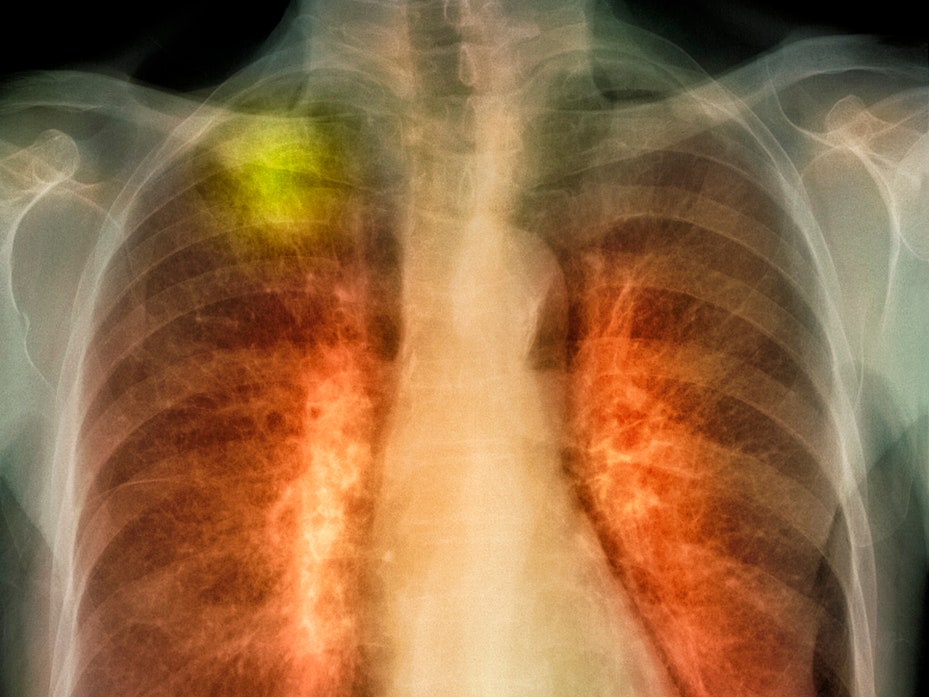

내시경을 기도로 넣어서 위장 안에 있는 점막을 눈으로 살피는 검사가 바로 위내시경 검사입니다. 비교적 다른 검사들보다 더욱 더 정밀하게 확인할 수 있다는 특징이 있습니다. 그러나 관을 직접 몸 안으로 넣어야 하기 때문에 무서움 때문에 많은 사람들이 주저하기도 합니다. 그래서 수면 내시경을 요즘 하시는 분들도 많습니다.

특별히 짜고 매콥한 음식을 많이 섭취하는 한국인들의 식습관 때문에 위장 관련 질환이 아주 높고 위암 발생률이 아주 큽니다. 저희 어머니께서도 위암으로 돌아가셨지요. 하지만 위암을 조기에 발견할 수 있도록 주기적으로 위내시경 검사를 하신다면, 조기발견 시 완치율이 90%를 왔다갔다한다고 하니 내시경 검사를 정기적으로 받으시는 것을 권장드립니다.

보통 40살이 되어서는 위내시경 검사를 2년에 1번꼴로 받는 것을 권장드리고, 안전한 조기진단으로 90%라는 완치율을 위해서라도 1년에 한번은 받아보는 것이 좋습니다. 더군다나 위장 관련으로 고생하시는 분들이나 가족력이 있으신 분들에게는 남녀노소를 따지지 않고 의사와 면담해서 내시경 검사의 적절한 주기를 설정하는 것이 좋습니다.